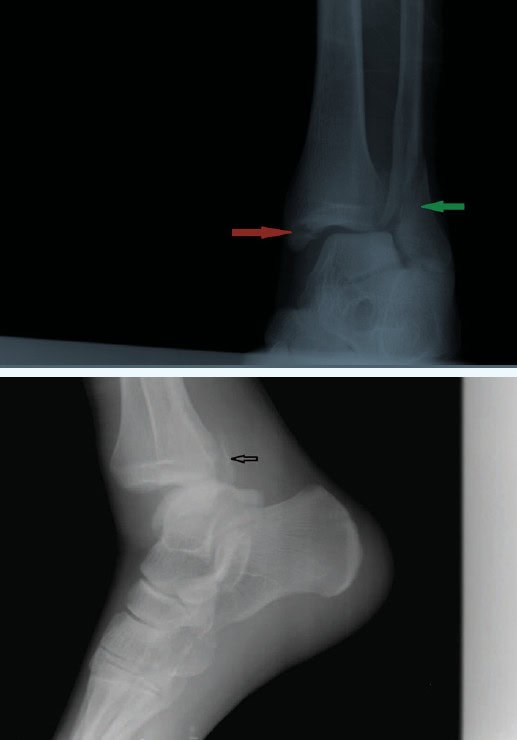

Diagnosis: The x-ray reveals a trimalleolar fracture of the ankle (arrows).

A trimalleolar fracture of the ankle involves the lateral malleolus (green arrow), medial malleolus (red arrow) and the distal posterior aspect of the tibia (black arrow). Ligament damage and dislocation are common. This is an unstable fracture and requires emergent orthopaedic consultation and adequate immobilization and analgesia in the urgent care center.